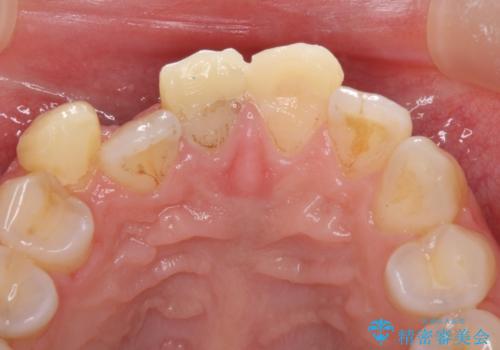

- 転倒により前歯の一部が欠けてしまったとのことで来院された患者様です。

神経が保存できる歯、神経を除去しなければならない歯、抜歯が必要な歯があり、ブリッジやインプラントなどによる治療を提案しました。

元々歯並びが気になっていたとのことで、前歯の治療を行うことを契機に矯正治療も行うこととしました。

本来であれば積極的に小臼歯を抜歯して口元を下げても良いのですが、前歯を1本抜歯しないといけなくなったため、非抜歯矯正をインビザラインを用いて行うこととしました。